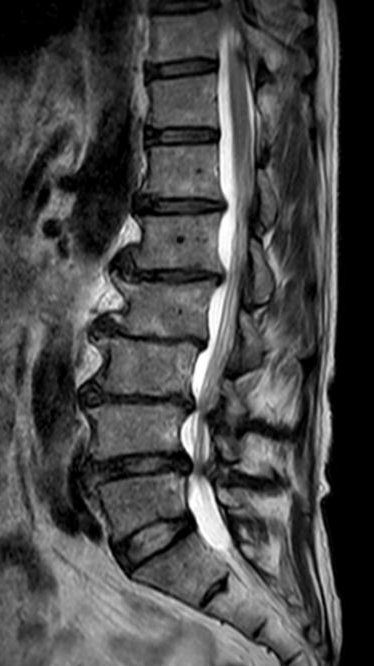

64岁的邱某因“腰痛多年,加重伴左下肢放射痛1月”来到昆山市中医医院脊柱骨科陈勇主任门诊就诊,经对患者的评估后,陈勇主任考虑其为“腰椎间盘突出症、腰椎椎管狭窄症”,随即安排住院治疗。

入院后,陈勇主任在科室组织了病例讨论并表示:常规保守治疗只能缓解症状无法从根本上解决病根。目前,患者已保守治疗1月,症状未见明显缓解,且进行性加重。影像学可见腰椎间盘突出伴椎管狭窄严重程度高,有明确的手术指征,结合患者及其家属的意愿,选择腰椎后路减压植骨融合内固定术。

▲术前MRI

既往脊柱外科医生仅能根据术前影像学资料制定手术方案,但3D打印技术的出现,可以客观、立体、快速地复制出患者目标脊柱的1:1实物模型,并可根据需要建立不同的剖面打印图,利于术者更直观地观察特定区域的骨、血管、脊髓神经等毗邻关系和个体化解剖特点,制定精细化、个体化的手术方案,从而在一定程度上提高了椎弓根螺钉置入或某些穿刺诊疗操作的精准性和安全性。